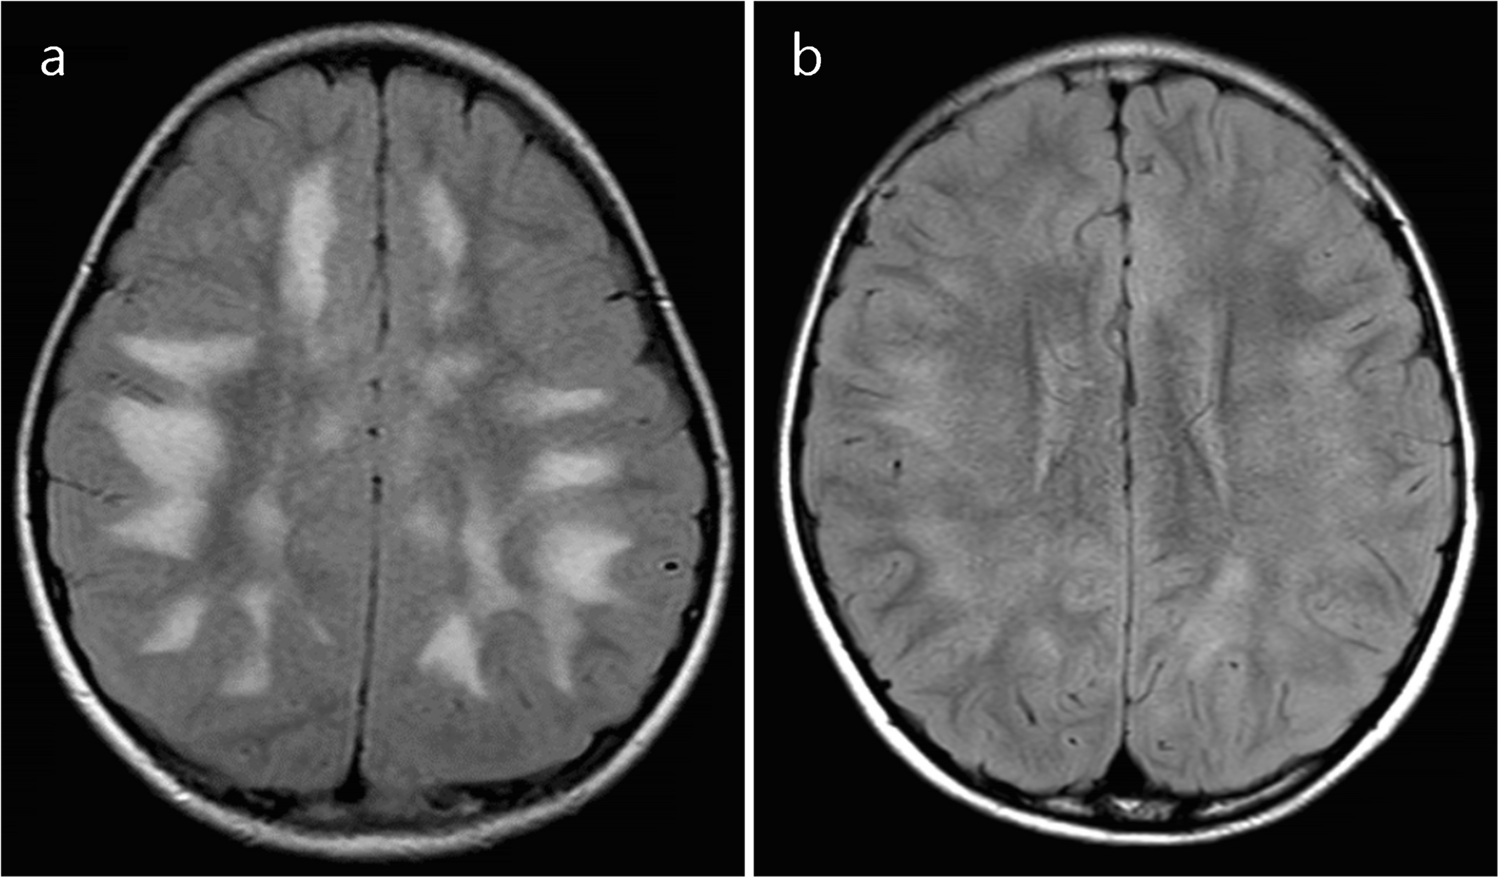

Typical ADEM on brain MRI was defined by the presence of bilateral, diffuse, poorly demarcated, large (> 1–2 cm) confluent lesions primarily affecting the cerebral white matter (Fig. 1) [23]. The following imaging features were considered atypical for ADEM [24]: unilateral lesions, well-defined lesions, exclusively small lesions (all < 2 cm), T1-hypointense lesions, lesions oriented perpendicular to the ventricles, lesions predominantly affecting the subcortical white matter more than the periventricular or deep white matter, and definite cortical involvement (Fig. 2). T1-hypointense lesions were defined as those appearing hypointense compared to gray matter on T1-weighted imaging. When evaluating lesion size, confluent lesions were regarded as large even if composed of multiple smaller aggregating lesions. Subcortical white matter lesions with suspected involvement of the adjacent cortex were not classified as cortical lesions.

Fig. 2

Representative magnetic resonance imaging features considered atypical for acute disseminated encephalomyelitis. a Axial T2-weighted image in a 5-year-old boy with myelin oligodendrocyte glycoprotein antibody-associated acute disseminated encephalomyelitis (MOG-ADEM) shows well-demarcated lesions predominantly involving subcortical white matter. b Axial fluid-attenuated inversion recovery image in a 5-year-old girl with MOG-ADEM shows small (< 2 cm) lesions. c Axial T1-weighted image in an 11-year-old girl with MOG-ADEM shows a T1-hypointense lesion (arrow) compared to gray matter. d Axial T2-weighted image in a 2-year-old girl with MOG-ADEM shows white matter lesions oriented perpendicular to the ventricles (arrows), appearing as laterally extending striations. e, f Axial T2-weighted (e) and fluid-attenuated inversion recovery (f) images in a 3-year-old boy with MOG-ADEM show cortical lesions (arrows)